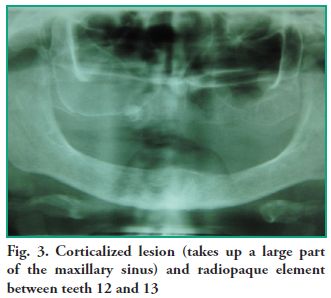

The clinical diagnosis reached was residual cyst, and the differential diagnosis was development cyst, odontogenic and non-odontogenic tumor, and mucocele. Periapical and occlusal radiographies, a teleradiography with a frontal Waters’ view, and an orthopantomography (OPG) were taken. The set of images showed a corticalized lesion measuring, on average, 25 mm in height and 35 mm in length, which is divided by a septum. There is a minor fenestration in the floor of the maxillary sinus, in the rearmost portion. There is also a radiopaque element near tooth 13 that is surrounded by a sharp, radiolucent halo (Fig. 3).

The clinical diagnosis reached was residual cyst, and the differential diagnosis was development cyst, odontogenic and non-odontogenic tumor, and mucocele. Periapical and occlusal radiographies, a teleradiography with a frontal Waters’ view, and an orthopantomography (OPG) were taken. The set of images showed a corticalized lesion measuring, on average, 25 mm in height and 35 mm in length, which is divided by a septum. There is a minor fenestration in the floor of the maxillary sinus, in the rearmost portion. There is also a radiopaque element near tooth 13 that is surrounded by a sharp, radiolucent halo (Fig. 3).